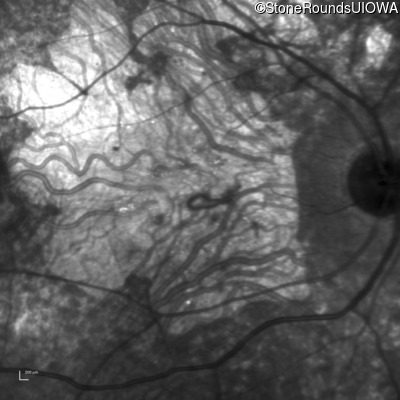

Age at visit: 30 years

This 30 year old man first noticed poor vision in dim light when he was five years old. His visual acuity began to fall in his early 20's.

Diagnosis & molecular findings

Disease Gene Allele 1 variant(s) Allele 2 variant(s) Inheritance mode

Macular Disease WDR19 His344Arg CAT>CGT Ser485Ile AGT>ATT AR